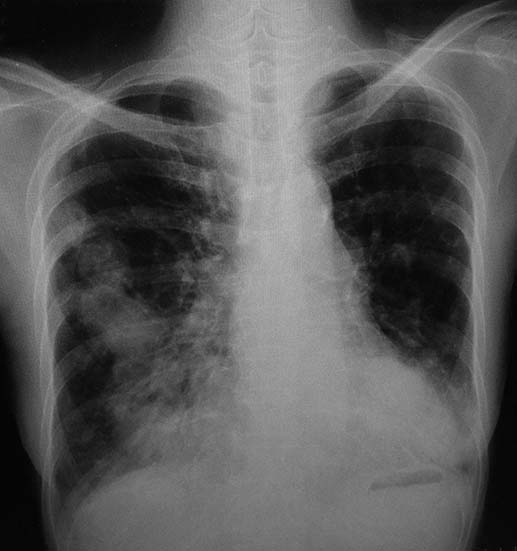

• X線検査では,通常,両肺の中・下部領域に多数の空洞化した転移性結節が認められる. 肺外への浸潤は極めて稀. 皮膚,中枢神経系,肝臓,腎臓などにも転移が見られる.

今月定期受診で1年ぶりにchest X-pを撮影. 両肺野に多発結節影が指摘されて受診となった.

chestX-pとCT.サムネイル画像クリックで大きな画像がみられます.